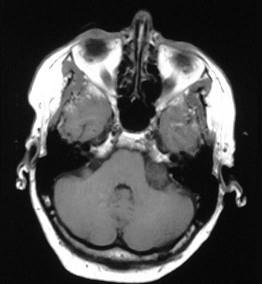

问题 桥小脑占位性病变(如图所示)的临床表现不包括下列哪项()

选项 A.患侧神经性耳聋伴有耳鸣及小脑症状 B.同侧面部感觉部分减退及轻度周围性面瘫 C.产生两眼上视障碍,少数有下视障碍 D.肿瘤较大时有后组脑神经症状 E.颅内压增高症状

答案 C